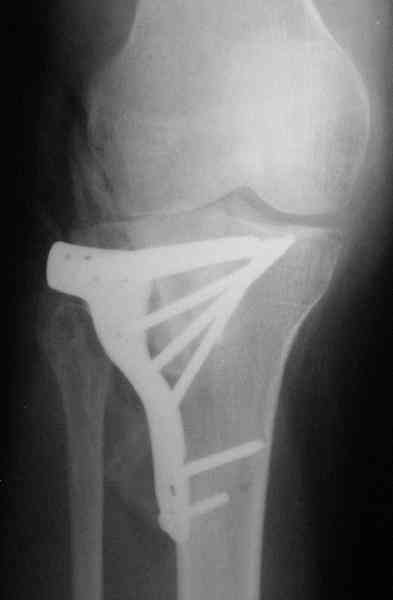

Уважаемый Абдурашид. Если нет противопоказаний , то из оперативных способов, я бы рекомендовал следующие: Полное замещение наружного мыщелка аллотрансплантатом либо открытая репозиция с элевацией и замещение дефекта ауто или аллокостью. В Ваших условиях , я бы рекомендовал второй способ. Во-время элевации необходимо разъединить фрагменты со стороны сустава ( надсечь скальпелем по линиям перелома, а затем тонким остеотомом их разъединить. При помощи долота произвести неполную остеотомию ( захватите не менее 1,5 - 2 см губчатой кости и поднять фрагменты, визуально отрепонировать и фиксировать 2-3 спицами. Дефект заместить костным ауто или аллатрансплантатом. Окончательная стабилизация пластиной ( лучше с угловой стабильностью, либо АВФ - позволит спокойно устранить угловую деформацию.

Через 3 месяца после перелома все еще можно выделить отломки, очистить от костной мозоли и и восстановить анатомию суставной поверхности. Фиксировать компрессионными шурупами. Важно помнить, что наружный мыщелок должен быть на 4-5 мм выше внутреннего. Передняя крестообразная связка обычно остается с частью кости и важно фиксировать ее проволокой по Ли. После восстановления суставной поверхности весь комплекс суставной поверхности нужно фиксировать к диафизу, можно использовать пластинку с фиксированными шурупами с наружной поверхности или две обычные с двух сторон или аппарат Илизарова. Важно сохранить задний наклон плато приблизительно 7 градусов. При закрытии доступа бугристость б.б кости фиксировать двумя шурупами. Важно добиться стабильности для максимально ранней разработки. Операция сложная, но интересная.

Наш план; доступ как подсказал Michael, по возможности репозиция, костная аутопластика дефекта метафиза, винты и спицы, АВФ и умеренная дистракция с шарнирными стержнями, и ранная пассивная разработка. Операцию планируем на следуюшей недели.